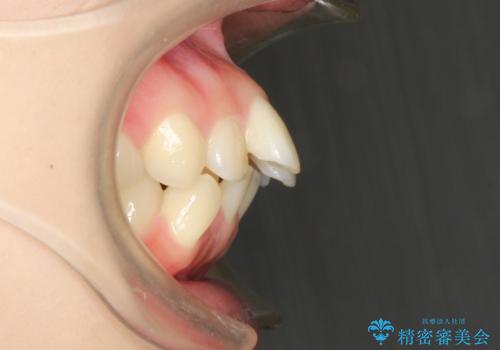

- 口元の突出感を気にして来院された患者様です。

上下左右の第一小臼歯4本を抜歯して口元を下げる治療計画としました。

目立たない装置が希望であったため、上顎が裏側装置である、ハーフリンガル装置を選択されました。